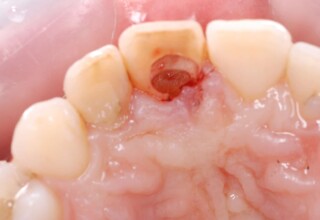

Αποκατάσταση Οπίσθιου Απονευρωμένου Δοντιού με Ανασύσταση Σύνθετης Ρητίνης

Η συνήθης αποκατάσταση ενός απονευρωμένου οπισθίου δοντιού είναι με μια στεφάνη. Ο κύριος λόγος είναι η προληπτική προστασία από κάταγμα και την επακόλουθη εξαγωγή. Σε πολύ συγκεκριμένες περιπτώσεις όπου εξειδικευμένα κριτήρια (κυρίως η ποσότητα της εναπομείνουσας οδοντικής ουσίας) ικανοποιούνται ή όταν η οικονομική δυνατότητα του ασθενή το επιβάλει, μια εκτεταμένη ανασύσταση συνθέτης ρητίνης μπορεί ν’αποκαταστήσει την αισθητική και λειτουργικότητα του δοντιού.